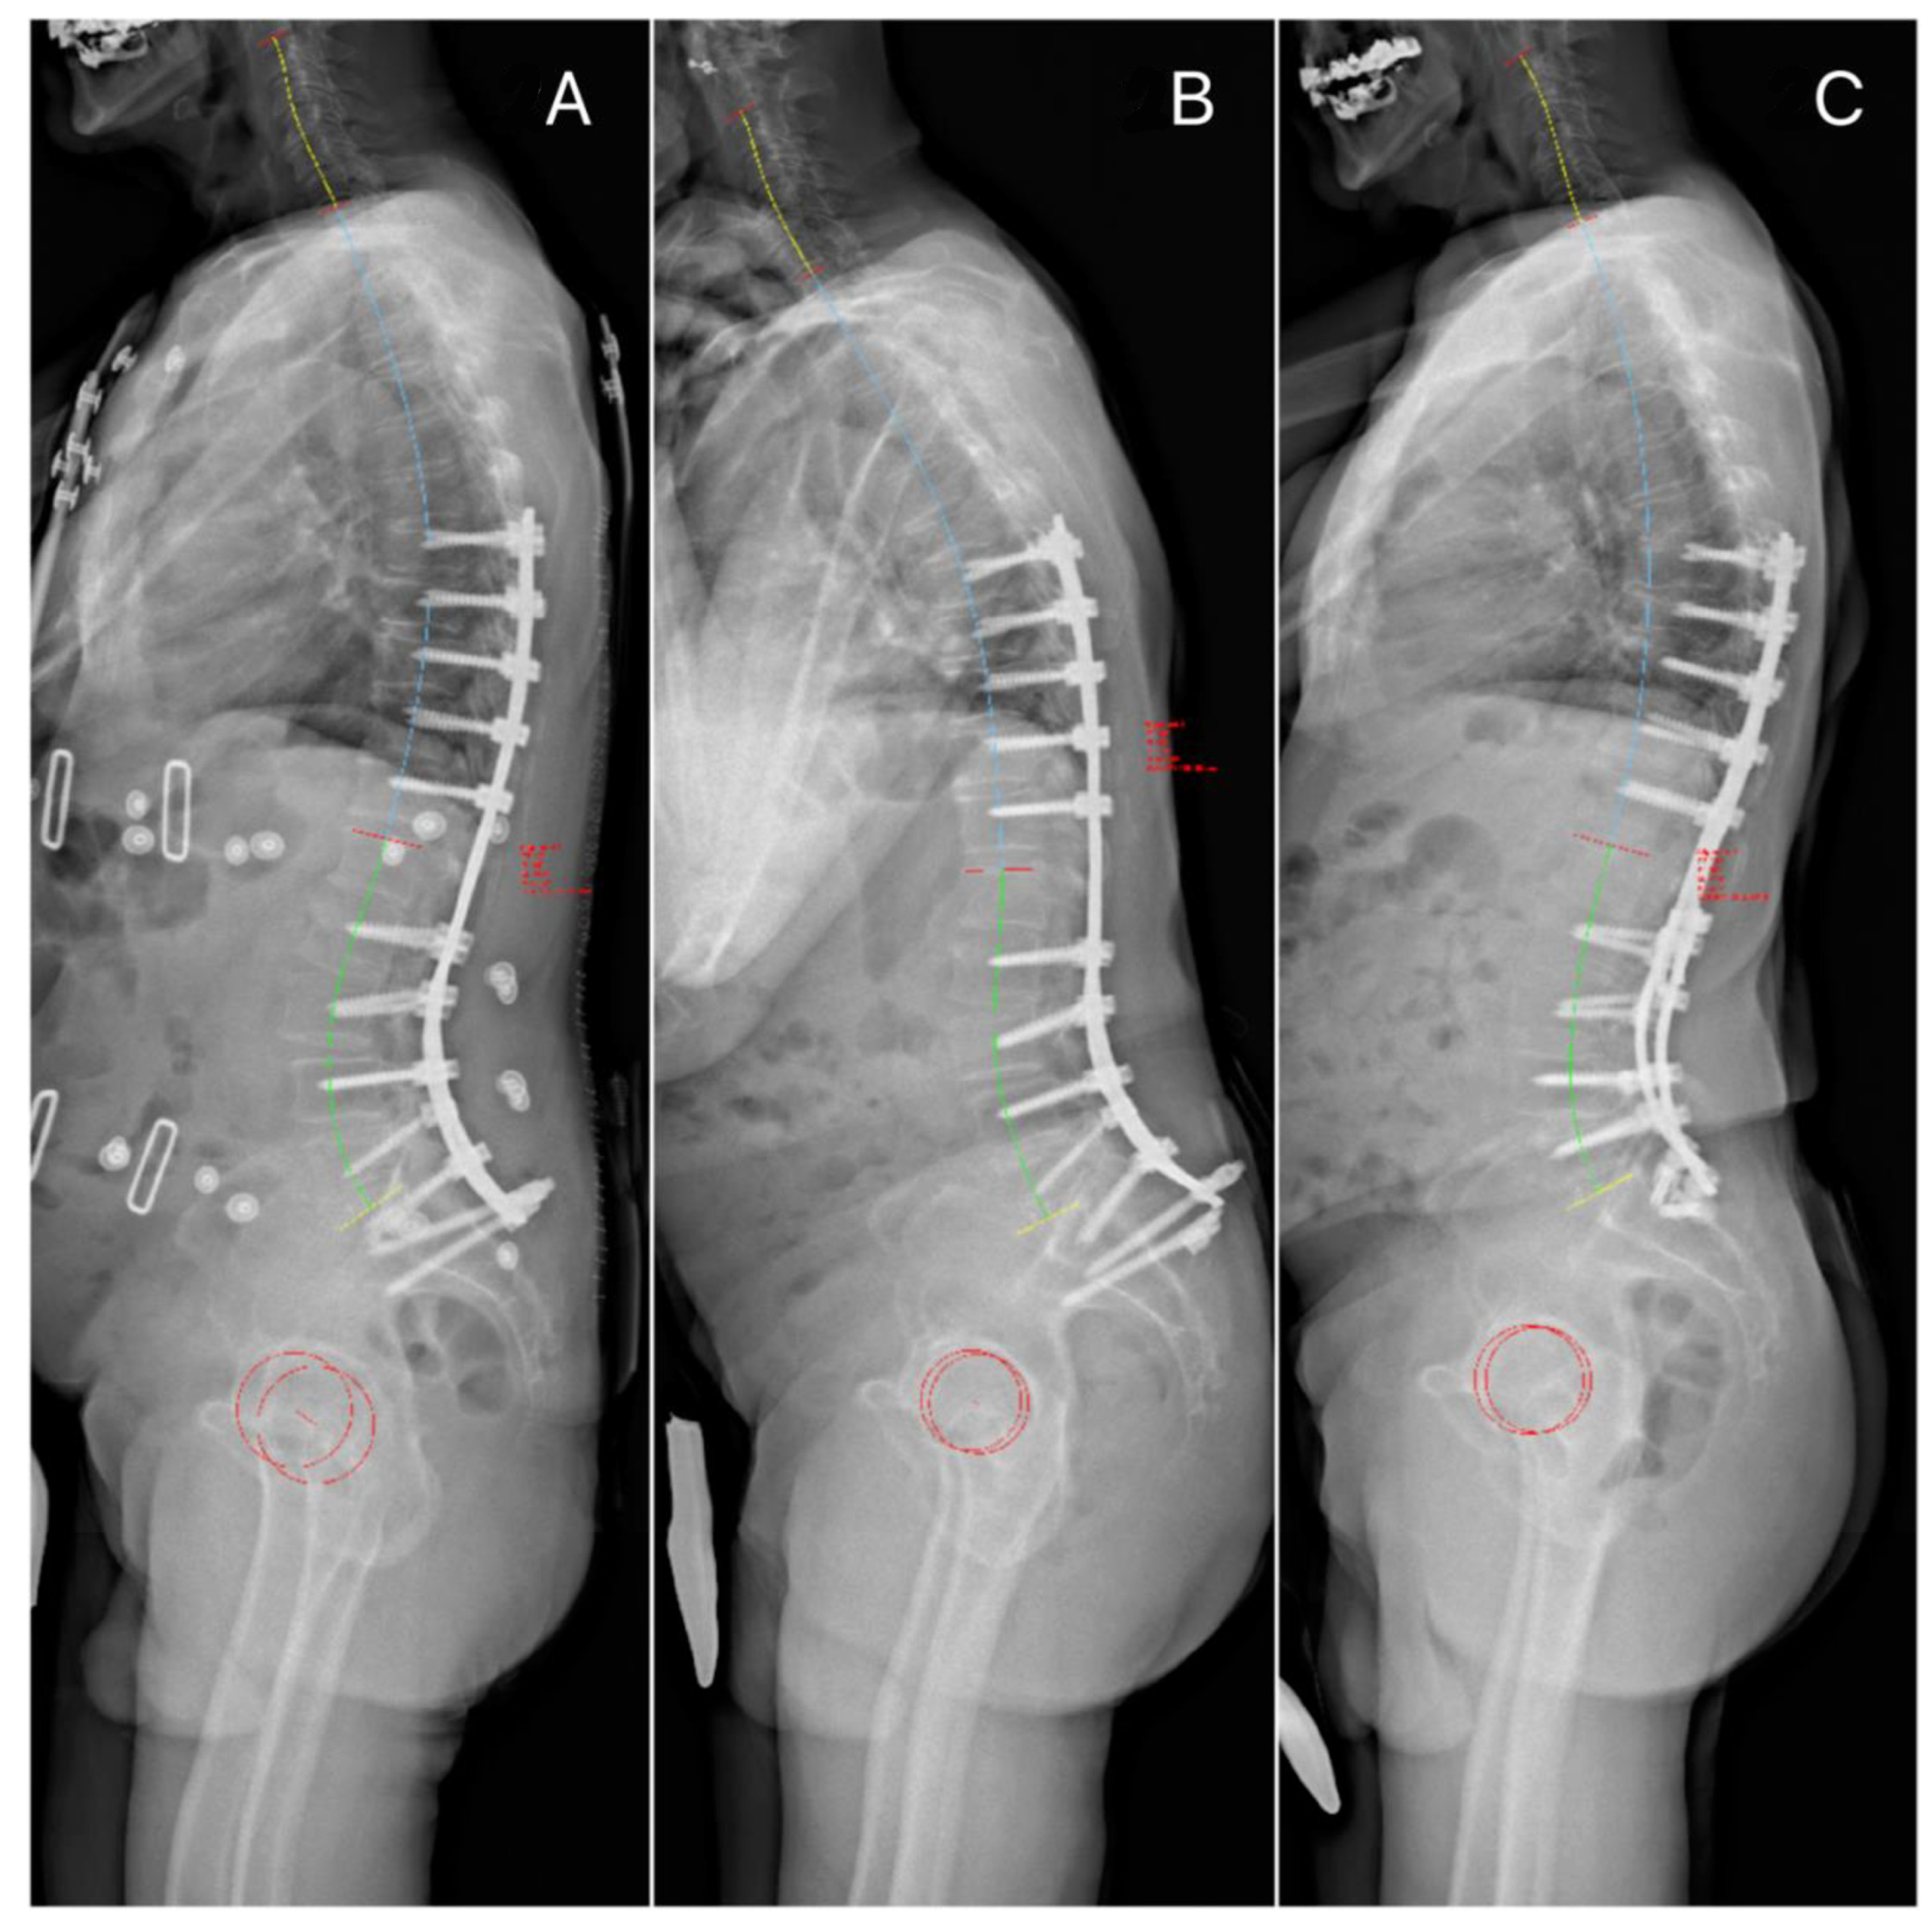

| SVA | 60.43 ± 55.24 | 37.64 ± 34.4 | 0.211 | 78.52± 64.57 | 41 ± 45.22 | 0.065 | 139.05 ± 20.53 | 126 ± 12.72 |

| PI | 53.93 ± 19.9 | 53.14 ± 12.6 | 0.413 | 54.42 ± 22.16 | 52.94 ± 19.53 | 0.984 | 71.5 ± 23.33 | 68 ± 24.04 |

| LL (L1S1) | 21 ± 28.1 | 32.62 ± 34 | 0.1 | 0.5 ± 34.86 | 15.3 ± 48.3 | 0.226 | 34.33 ± 36.67 | 62.5 ± 3.53 |

| PI-LL | 30.79 ± 20.9 * | 9.81 ± 11.7 * | 0.013 | 31 ± 27.67 | 9.64 ± 18.04 | 0.0548 | 11.67 ± 11.71 | 5.5 ± 20.50 |

| SS | 21.1 ± 15.05 | 23.1 ± 16.4 | 0.378 | 13.5 ± 17.09 * | 25.37 ± 16.13 * | 0.022 | 28.67 ± 19.50 | 54.5 ± 16.26 |

| PT | 30 ± 14.2 | 24.4 ± 8.1 | 0.129 | 34.75 ± 17.17 * | 22.06 ± 14.52 * | 0.032 | 22 ± 19.67 | 13.05 ± 7.77 |